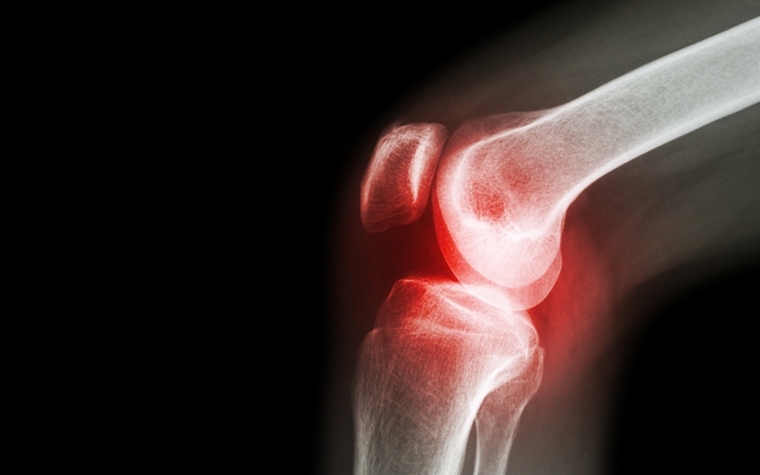

The European Commission recently announced it has approved the Amgen’s Amgevita, an anti-inflammatory drug, for sale in more than two dozen member nations.

The drug's approval in Europe, as well as its approval in the United States in September, were based on outcomes from clinical trials that studied the medicine’s use in plaque psoriasis, arthritis and Crohn’s disease, among both adult and pediatric populations.